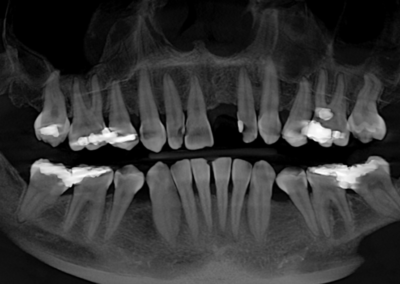

We start with a comprehensive full mouth examination, digital X-rays, a dental 3D(CBCT) scan and Trios5 Scan. The scanned images provide high-resolution images in a three dimensional plane. We use these images and scans for precise treatment planning.